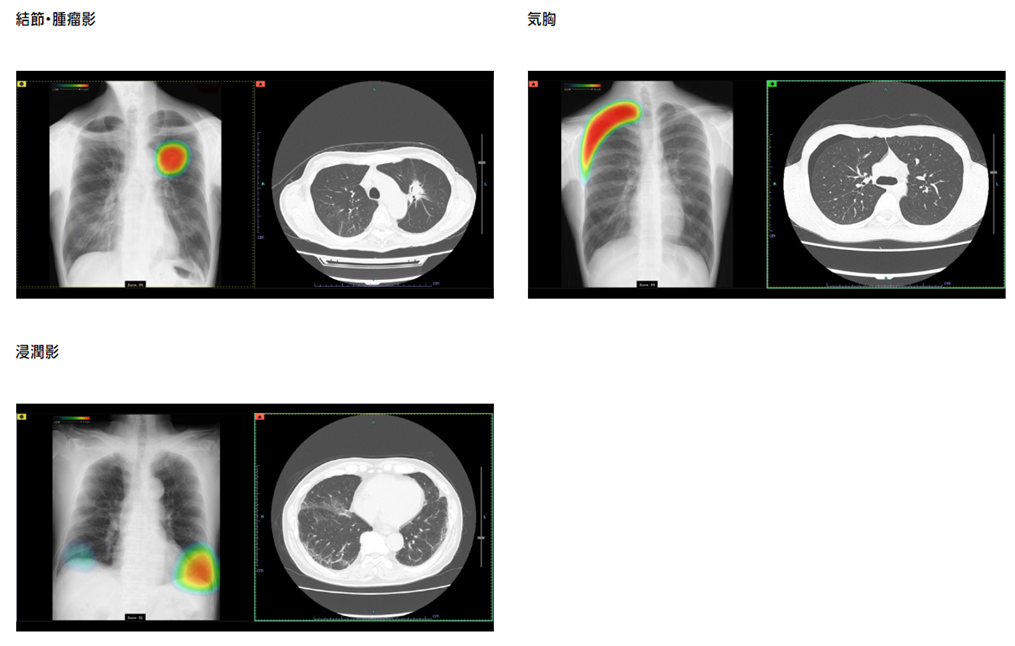

一方で胸部レントゲンではがんを疑う結節影だけでなく、肺炎や肺結核、肺気腫、間質性肺炎、気胸などいろいろ異常な影を診断する必要があります。AIによっては陰影が「ある、なし」だけでなく質的な診断もできる様になってきました。私のクリニックも富士フィルムの画像診断システム(PACS)に胸部X線画像病変検出ソフトウエアである「CXR-AID」を導入することになっており、結節・腫瘤、浸潤影(肺炎などで見られる広がりのある陰影)、気胸(肺の表面に穴があいて、肺と胸壁の間に空気が漏れて肺が潰れた状態)の3種類の病変が検出可能とされています。